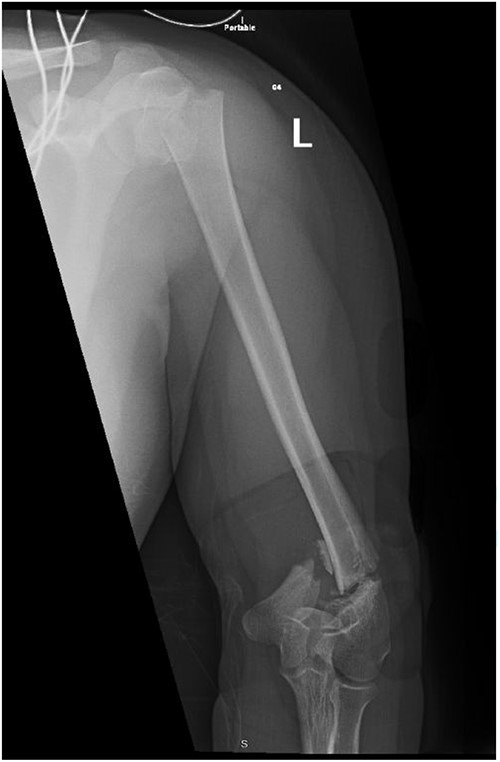

Upon arrival the patient underwent exploratory laparotomy followed by irrigation and debridement of both femur and humerus and application of external fixators (Fig. 2). The patient was admitted to the intensive care unit (ICU). Two days later, the patient underwent open reduction and internal fixation of both proximal and distal humerus (Fig. 3).

Anteroposterior (AP) view of the left humerus and elbow after Ex-fix application.